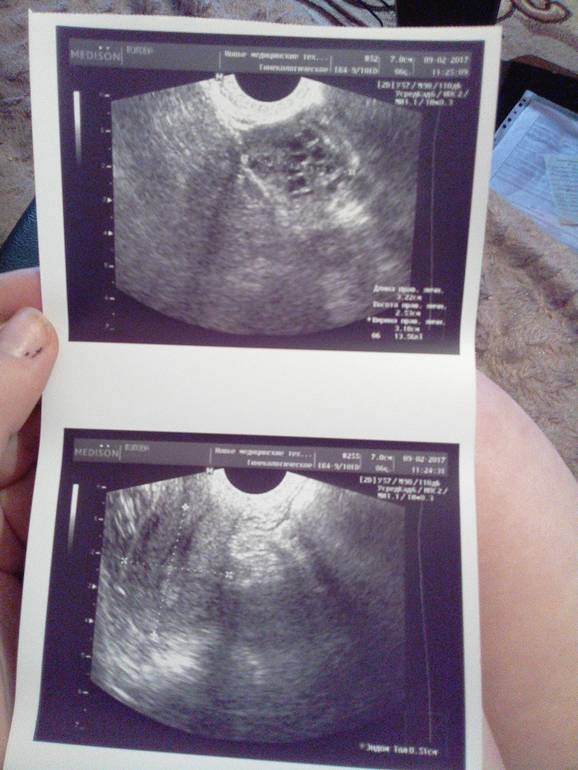

Девочки как УЗИ кто нибудь расшифрует?

Поликистоз яичников возможно

Но лучше врач скажет

Похоже что у вас цикл не стабилен

у вас написано что эндометрий второй фазы. вы не после М делали узи?

Скорее всего у вас высокий АМГ и созревает много фолликулов. Это лучше, чем когда их нет. Ничего страшного в этом нет. Не надо пугаться))). Но АМГ смотрят в соотношении с ФСГ.